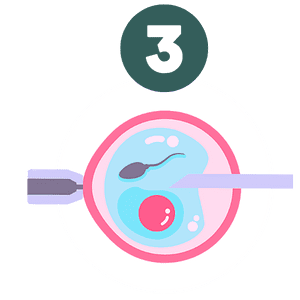

O processo de análise começa com a observação detalhada das imagens geradas pelo ultrassom morfológico. Isso inclui verificar a normalidade do útero, a integridade da placenta, membranas uterinas, o desenvolvimento fetal, a adequada frequência cardíaca fetal e o fluxo sanguíneo útero-placentário-fetal. O ultrassonografista avalia a anatomia do bebê, certificando-se de que os ossos, órgãos e outros sistemas, como o coração, cérebro, estômago e rins estejam se desenvolvendo conforme esperado. É igualmente importante observar a presença de batimentos cardíacos regulares e os movimentos respiratórios fetais no terceiro trimestre da gestação.

- Coração: Análise da anatomia e dos batimentos cardíacos.

- Fluxo sanguíneo: Inspeção dos vasos sanguíneos e da circulação.